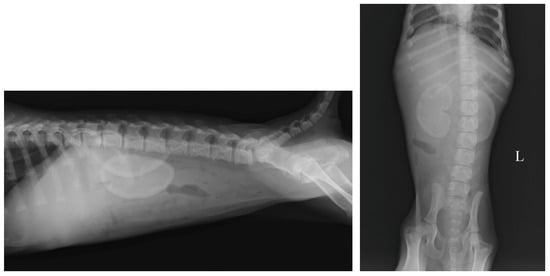

2.3. Imaging Findings